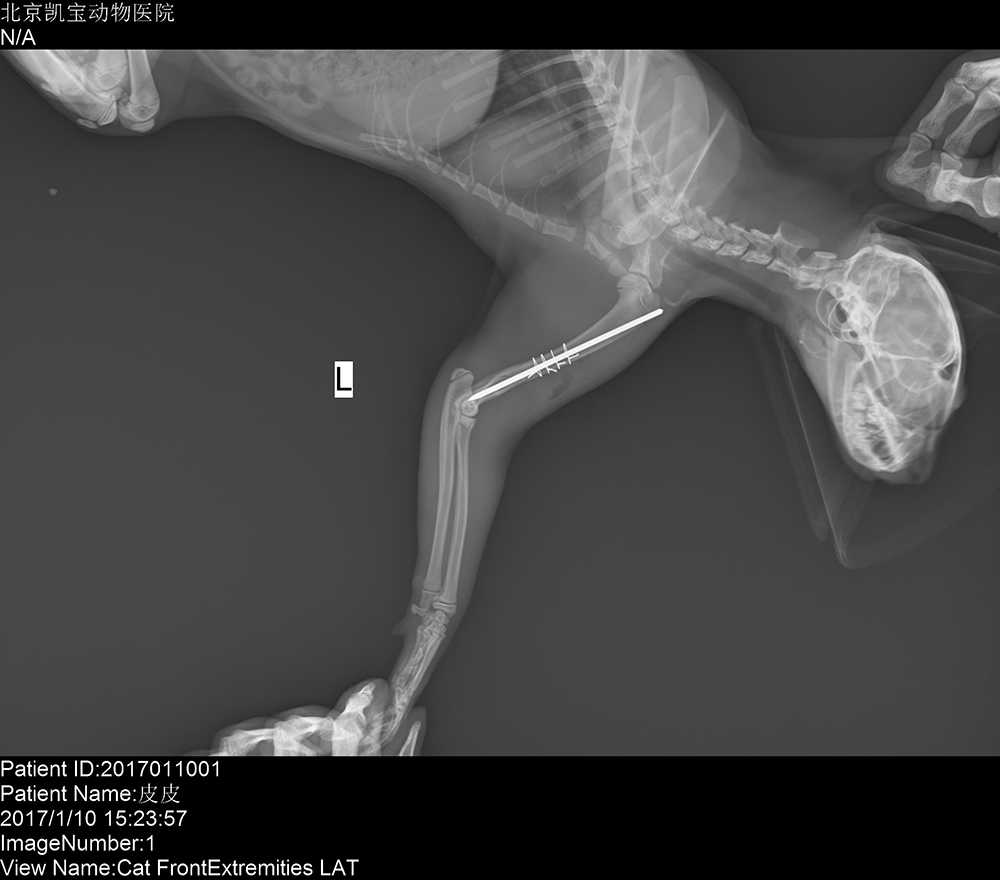

北(běi)京凱寶動物(wù)醫(yī)院 2017/1/15 上(shàng)一(yī)篇: 北(běi)京芭比堂動物(wù)醫(yī)院順轶分(fēn)院 下(xià)一(yī)篇: 北(běi)京芭比堂動物(wù)醫(yī)院緣愛(ài)分(fēn)院